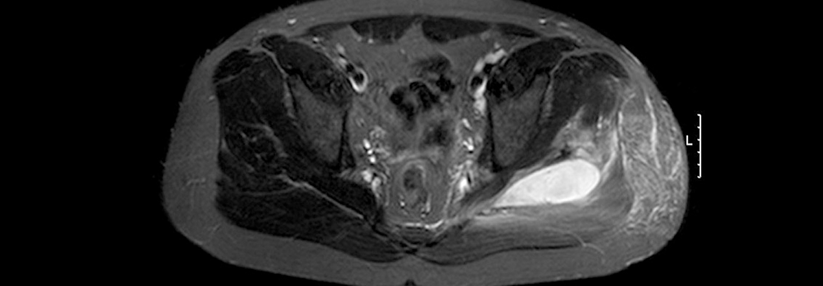

In dieser Situation half der Muskel­ultraschall, den Verdacht auf eine IBM zu erhärten. In der Myosonografie zeigten sich nahezu ubiquitär erhöhte Echogenitäten als Hinweis auf einen fettig-fibrösen Umbau der Muskulatur. Besonders betroffen waren M. biceps brachii, M. flexor digitorum prof., M. quadriceps femoris und M. gastrocnemius caput mediale. Die Elektromyografie, eine MRT der Oberschenkel sowie eine Muskelbiopsie bestätigten die Diagnose.